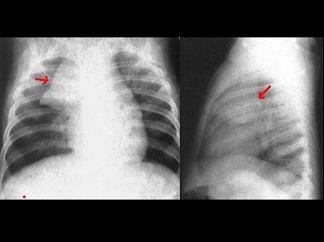

男性,10岁。胸闷、气短,呼吸困难。X线检查如图,最可能的诊断为()

A.心包炎

B.心包积液

C.先天性ASD

D.先天性VSD

E.心肌炎